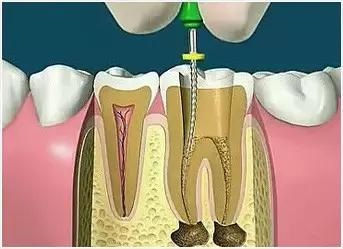

4、根管预备

根管清理成形的目的是去净根管壁上的感染物,通过根管器械的切削作用去除感染的牙本质并清理根管壁细菌以利于根管充填。